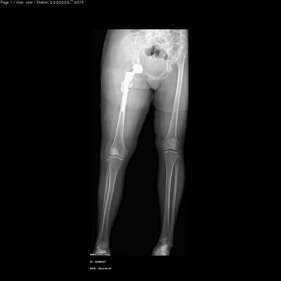

shortening osteotomy and total hip replacement for bilateral severe dysplasia of hip with high riding